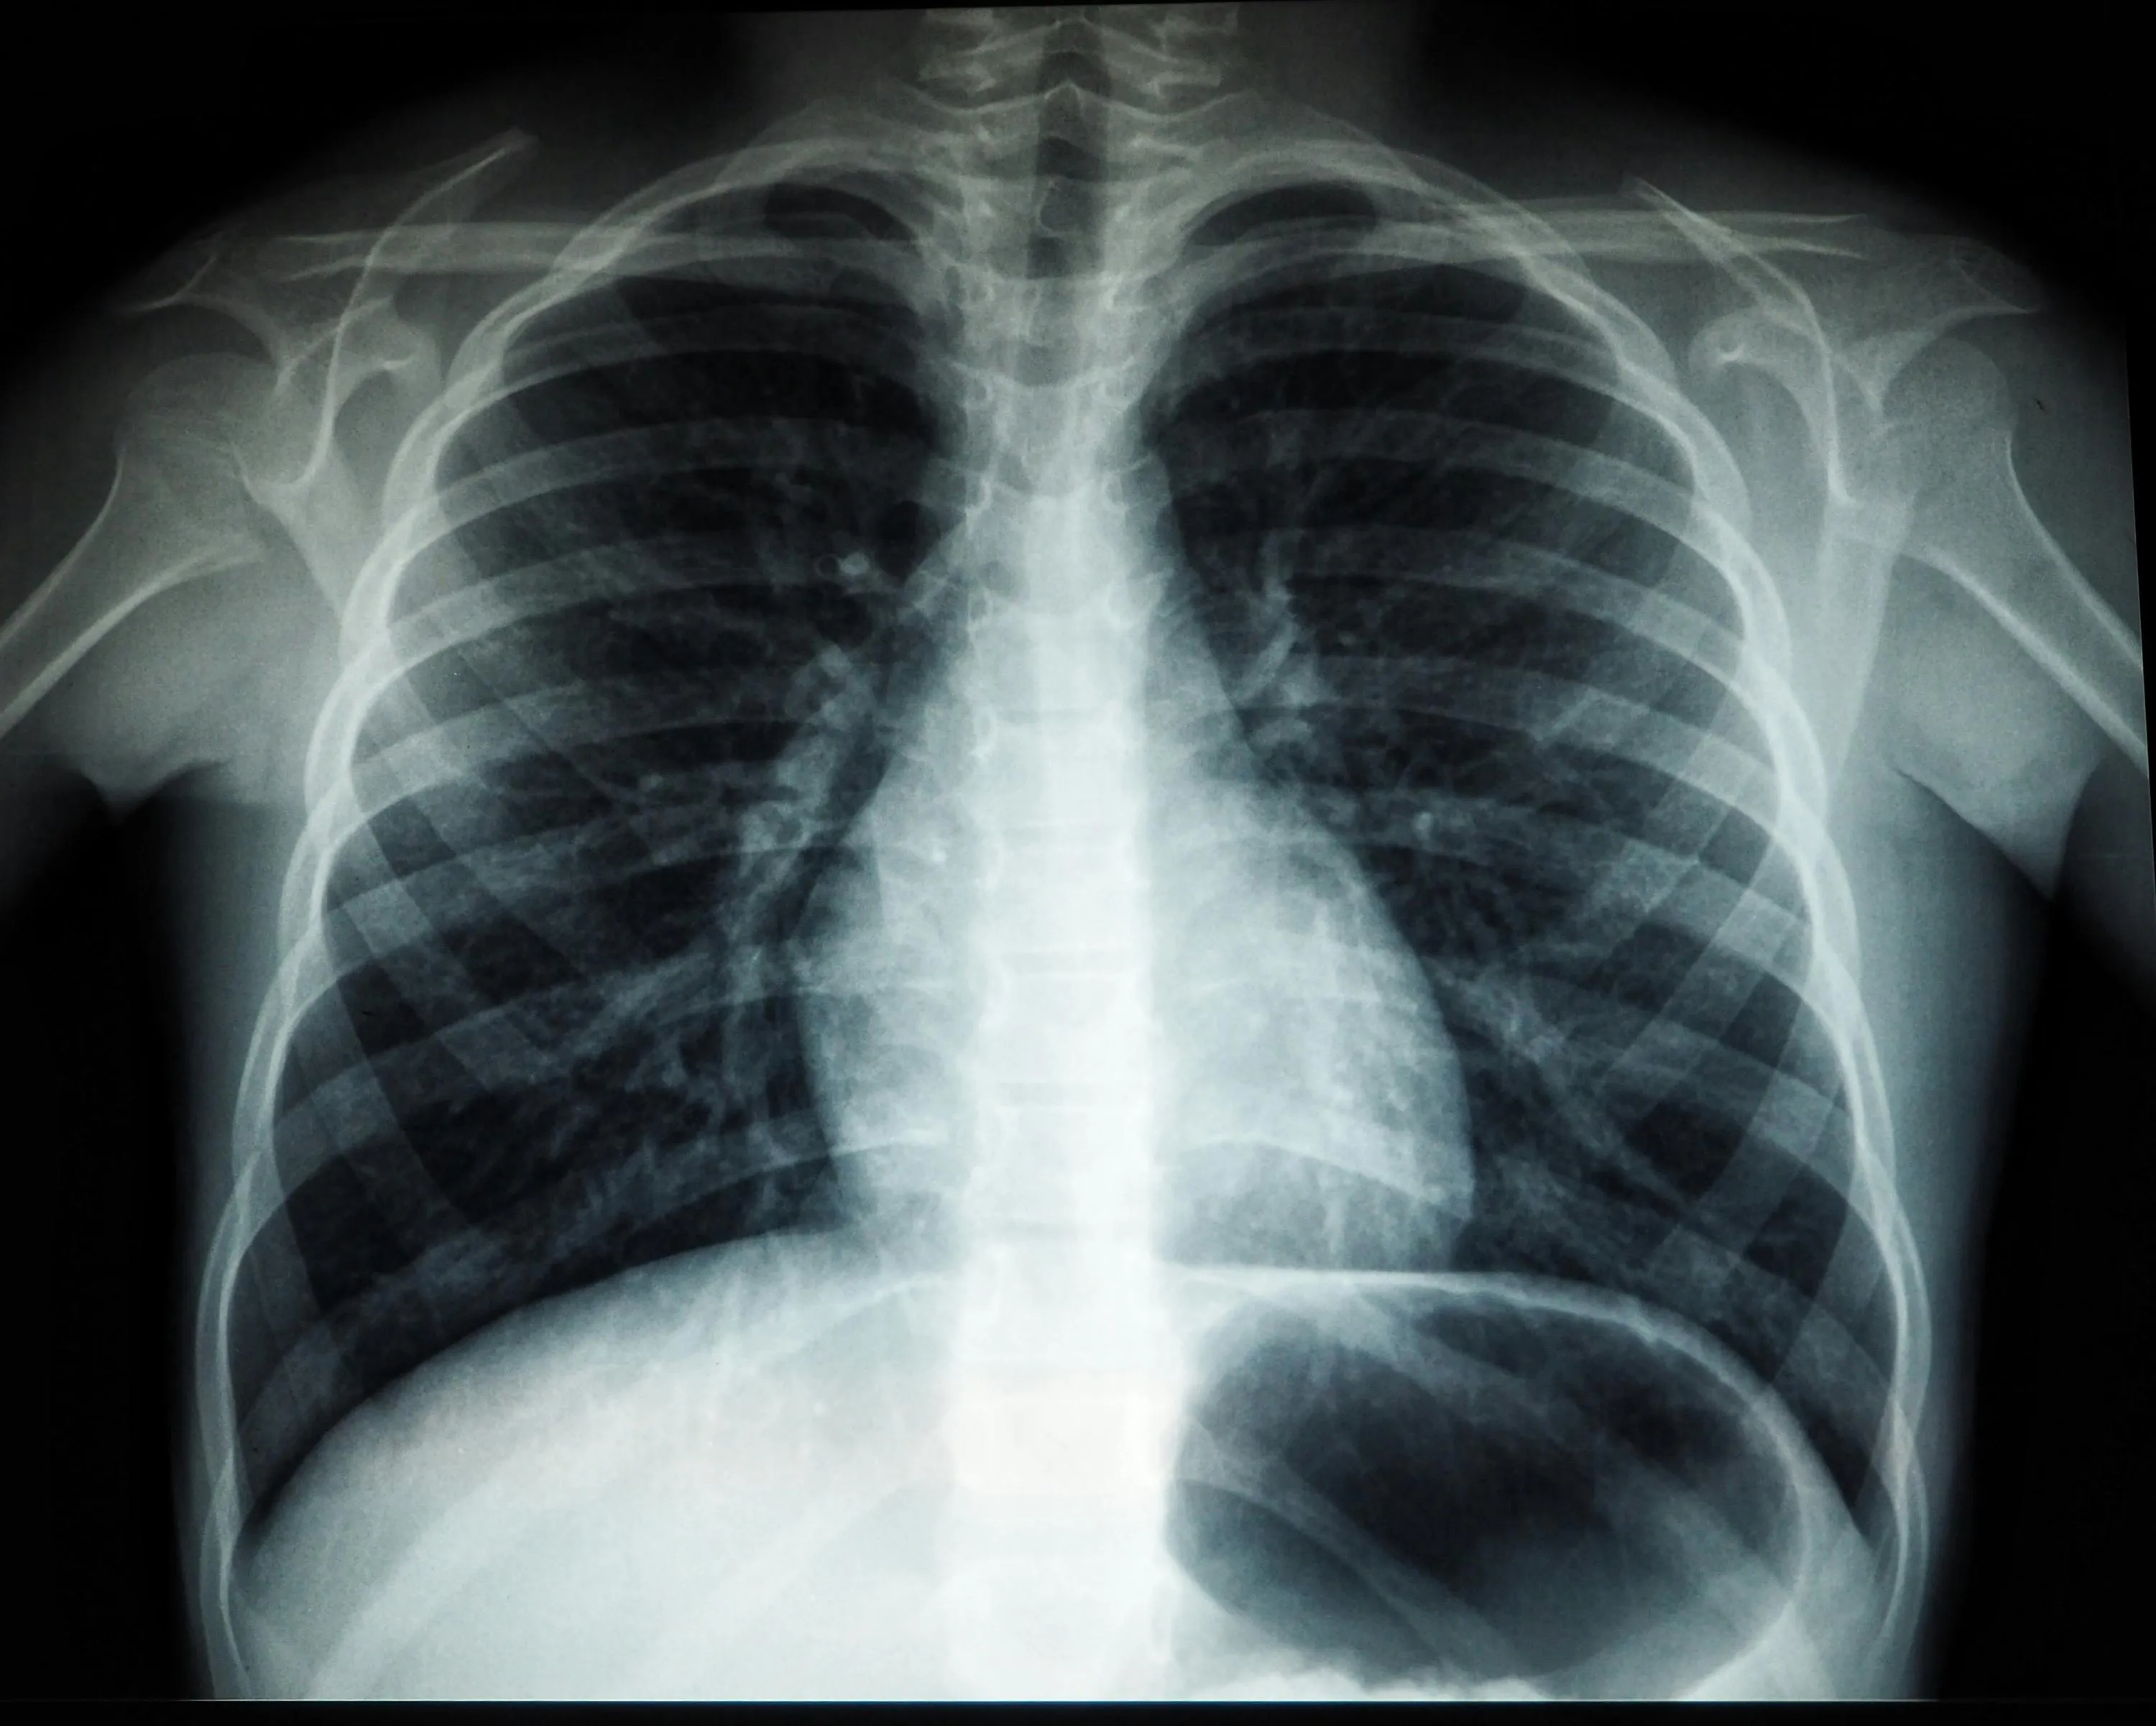

Рентген

Рентгеновское излучение – это форма электромагнитного излучения, что используется в медицине. Оно очень необходимо для диагностики заболеваний. Его открыл Вильгельм Конрад Рентген в 1895 году, когда проводил эксперименты с катодными лучами. Когда он заметил флуоресцентное свечение на экране, он случайно наткнулся на рентгеновские лучи, хотя и не искал их.

Рентген изобрели в 1895 году / Фото Unsplash (Umanoide)